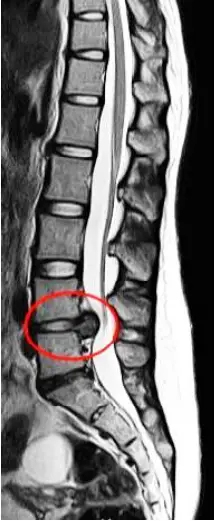

43歲男性,因為彎腰搬重物,導致嚴重下背疼痛,且其疼痛由左側臀部往下延伸之左側小腿,尤其前外側部分像針刺的麻痛感更為明顯,理學檢查發現:左側足背曲屈(dorsiflexion)的力量明顯比右邊弱,核磁共振如附圖所示,診斷為腰椎椎間盤突出,其最可能壓迫的神經為何?

椎間盤突出(herniated disc)最常壓迫的是通過(traversing)而非退出(exiting)的神經根。L4–L5水準的椎間盤突出偏好壓迫L5神經根,造成L5神經根所支配區域的放射痛、感覺異常及肌力減退。

影像為脊椎T2軸面及矢狀面MRI(紅框處標示於L4–L5)。可見:

- 椎間盤中央及偏盲側(paracentral)向後突出,穿透後縱韌帶並進入椎管。

- 突出的髓核壓迫硬膜囊及其下方通過的神經根。

- 其水準對應腰椎第四至第五節段,因此被壓迫的應為自此處通過之神經根(即L5神經根)。

選項C:L5

L4–L5突出壓迫L5通過根。臨床上可見:前外側小腿及足背的麻痛,並伴有足背屈(dorsiflexion)力量減弱,符合L5神經根病變表現,也是正確答案。 ([premiaspine.com](https://premia